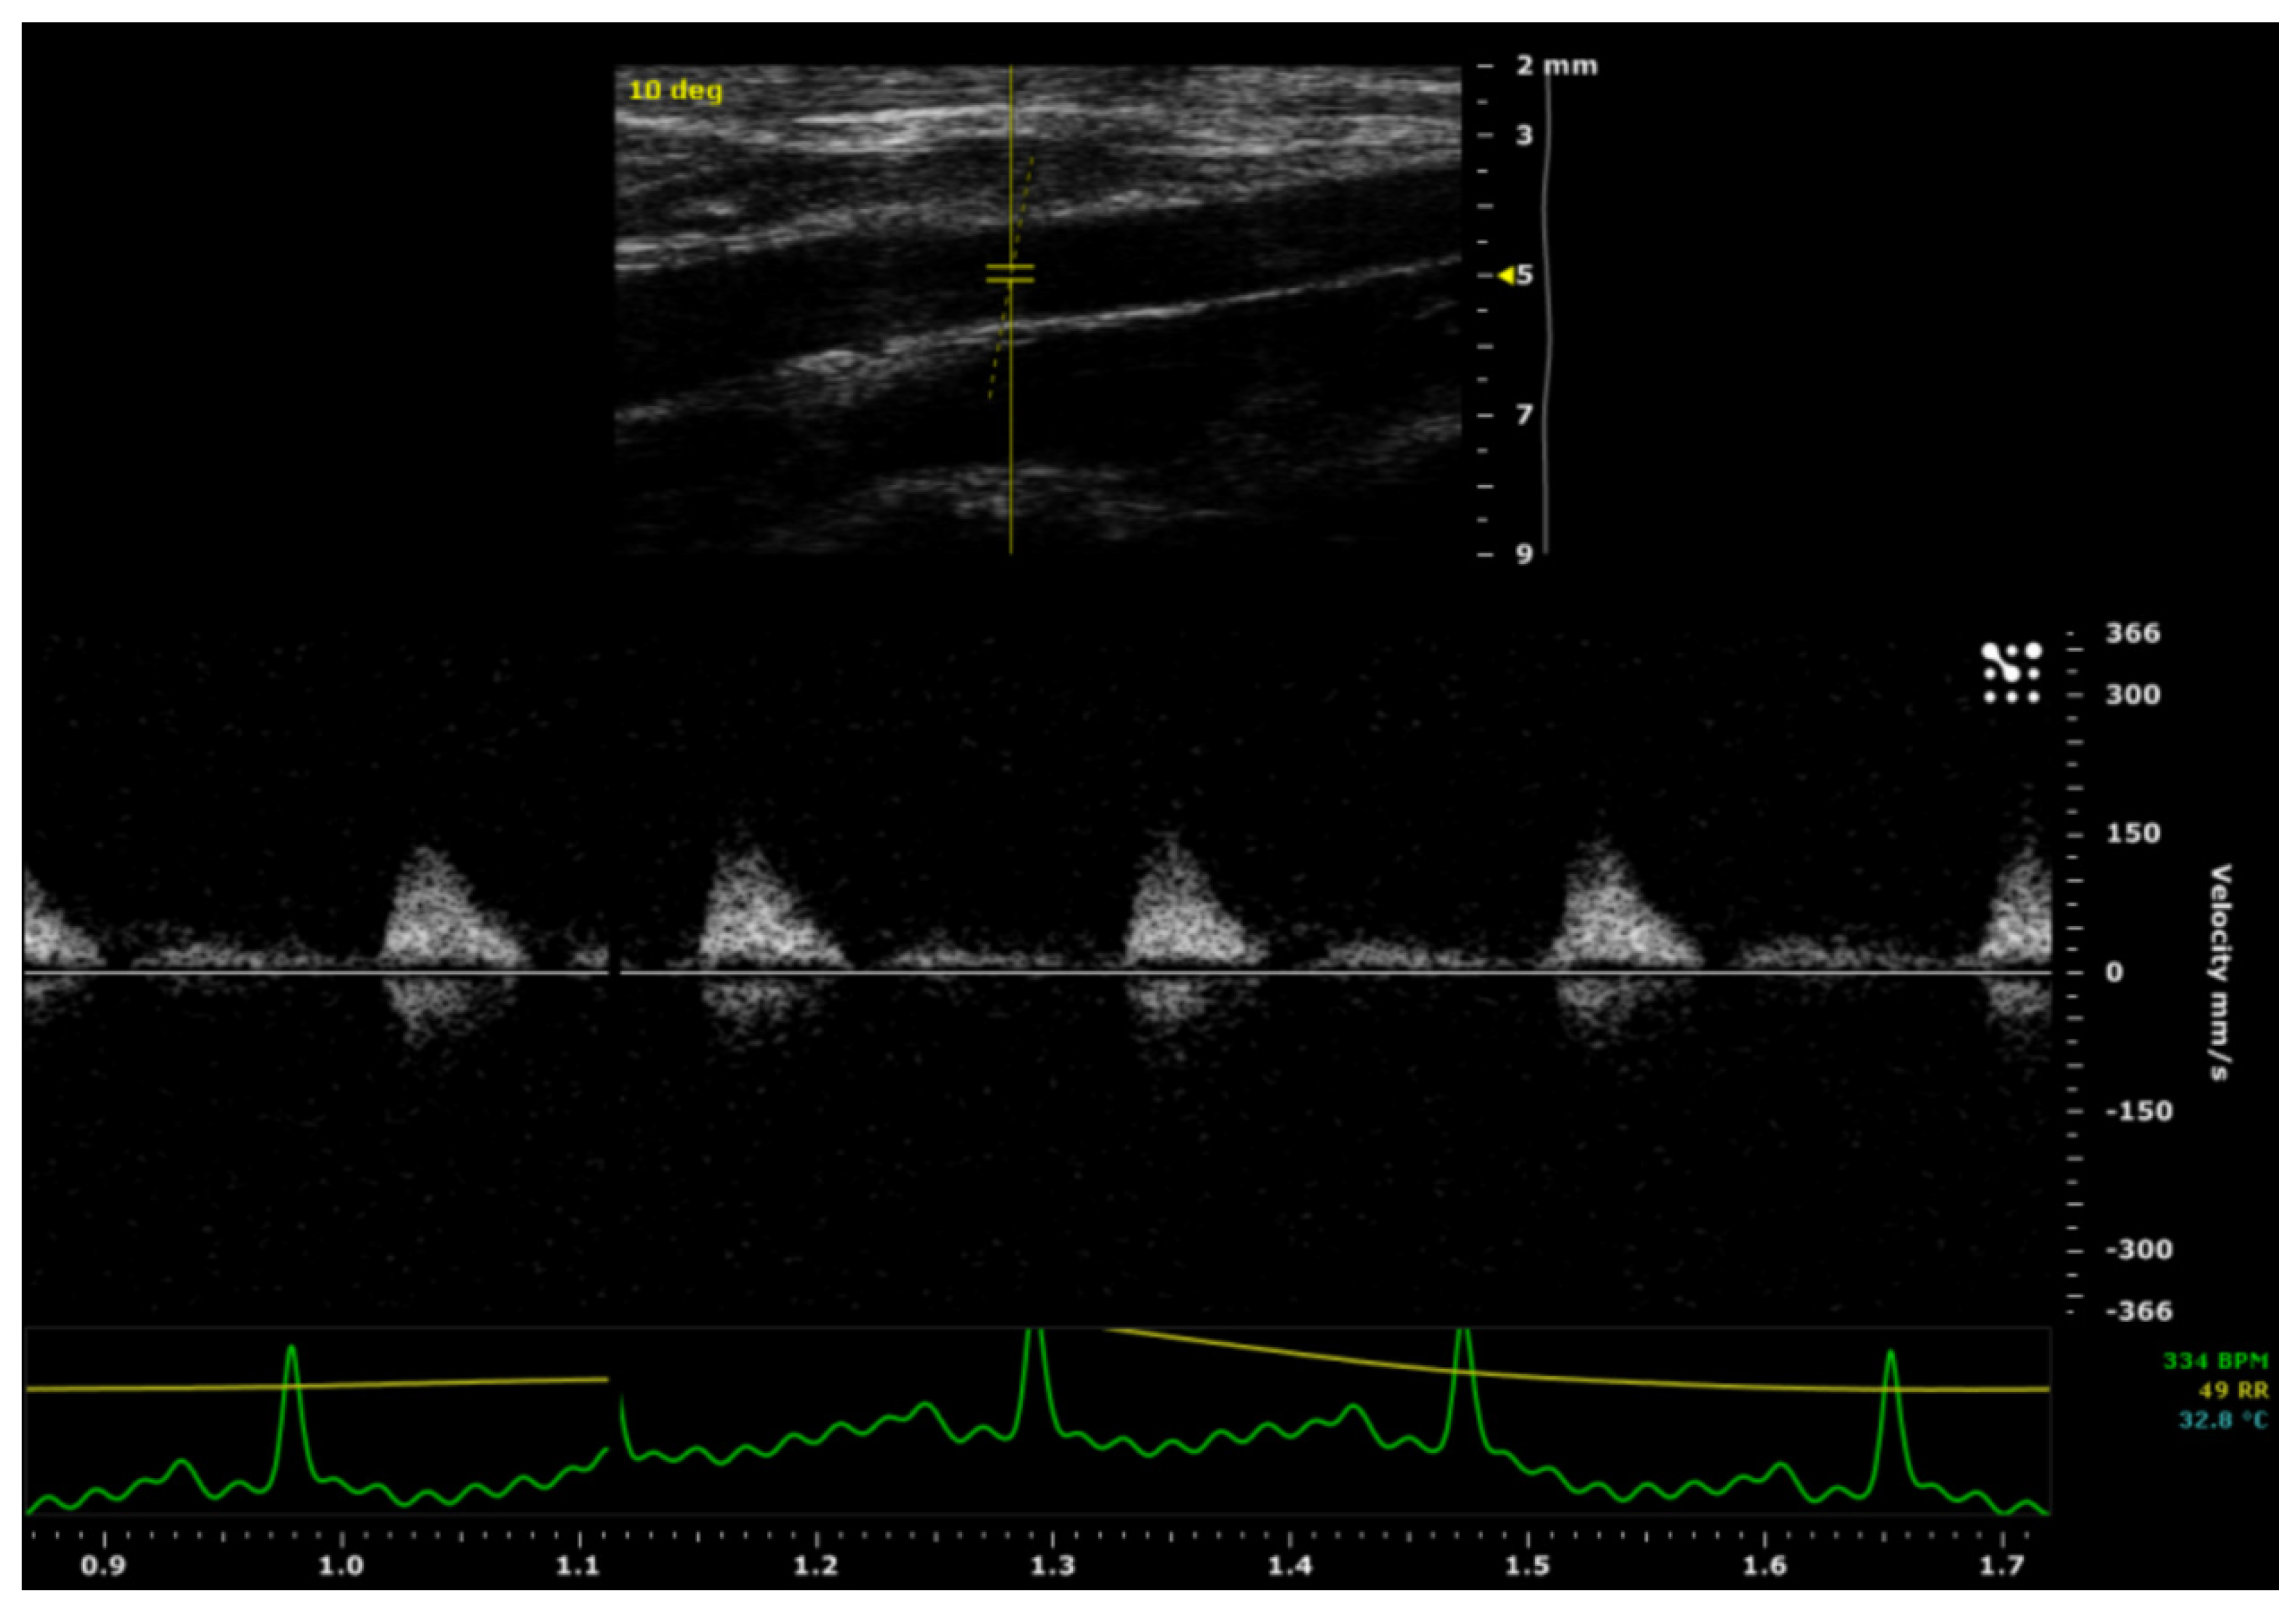

In vivo evaluation of patency in the intervention and control group was performed after a four- month-period using an ultrasound system (Visualsonics, Vevo® 2100, Amsterdam, The Netherlands). This system operated at a high frequency (13-75 MHz) with a spatial resolution of ~30 microns and a temporal resolution of 1000 frames/sec. Ultrasound imaging on the rats was performed under general anesthesia using sevoflurane (5 % induction and 2 % maintenance, Sevorane® Abbvie, Wavre, Belgium) in an O2 enriched gas mixture. The abdomen was shaved and ultrasound gel at 37°C was applied. The probe was levelled perpendicular to the spine. Using pulsed-wave 40MHz Doppler in the coronal plane, patency was categorically evaluated by the presence (patent) or absence (non-patent) of pulsatile arterial flow in the aorta segment distal to the graft/control aorta. Absolute maximal flow velocity (Vmax) and Vmax decay from the proximal to distal graft/control aorta were measured in the sagittal plane and expressed as the mean ±SD (in mm/s). The inner/outer, proximal/distal diameters and systolic/diastolic diameters of graft/control aortas (IDps, IDpd, IDds, IDdd, ODps, ODpd, ODds and ODpd) were measured using the Motion-mode (in µm) and compared between the groups. Images were analysed using ImageJ software (ImageJ, National Institutes of Health). The systolic expansion was calculated using the formula [IDps - IDpd] for the proximal segment and with [IDds - IDdd] for the distal segment. The proximal to distal decay in graft/control aorta expansion [(IDps-IDpd) – (IDds-IDdd)] was calculated and compared between groups.

After a four-month-period, a pulsed-wave Doppler ultrasound was used to evaluate the patency of the ePU graft/control aortas. There was a pulsatile arterial flow in all aorta segments located distally from the graft/control aortas. No stenotic processes were detected over the course of the graft/control aortas and there was no evidence of ePU graft-related complications, such as graft rupture or aneurysm formation. The rat with paraparesis was clinically considered to be graft failure/non-patent, bringing the overall patency of the intervention group to 8/9 (89 %) compared to 9/9 (100 %) in the control group. Therefore, there was no significant difference in patency between the intervention and the control groups. The ultrasound imaging of the ePU grafts is demonstrated in Figure 4.

There was no statistically significant difference between the intervention and control group for the absolute Vmax in the proximal aorta (p= 0.479) and the absolute Vmax in the distal aorta (p= 0.711). However, there was a statistically significant difference (p= 0.010) in Vmax decay (from proximal to distal), between the intervention group (mean= 49 ± 40 mm/s) and the control group (mean= -14 ± 39 mm/s). These data are shown in Table 1.

There was no statistically significant difference (p= 0.280) in proximal aortic systolic expansion between grafts (mean= 123 ± 49 µm) and shams (mean= 157 ± 75 µm). Neither was there a significant difference (p= 0.827) in distal aortic systolic expansion between the intervention group (mean= 104 ± 64 µm) and control group (mean= 114 ± 102 µm). There was also no statistically significant (p= 0.353) difference between the intervention and control group concerning the aortic expansion decay between proximal and distal aorta [(IDps-IDpd) – (IDds-IDdd)]. However, the means showed a relevant difference between the intervention group (mean= 52 ± 110 µm) and the control group (mean= 9 ± 75 µm). These data are summarized in Table 1.

Figure 4. Ultrasound imaging of an ePU graft. Velocity of aortic blood flow, measured using pulsed-wave Doppler (left) and aortic pulsatile expansion, measured using Motion-mode (right).